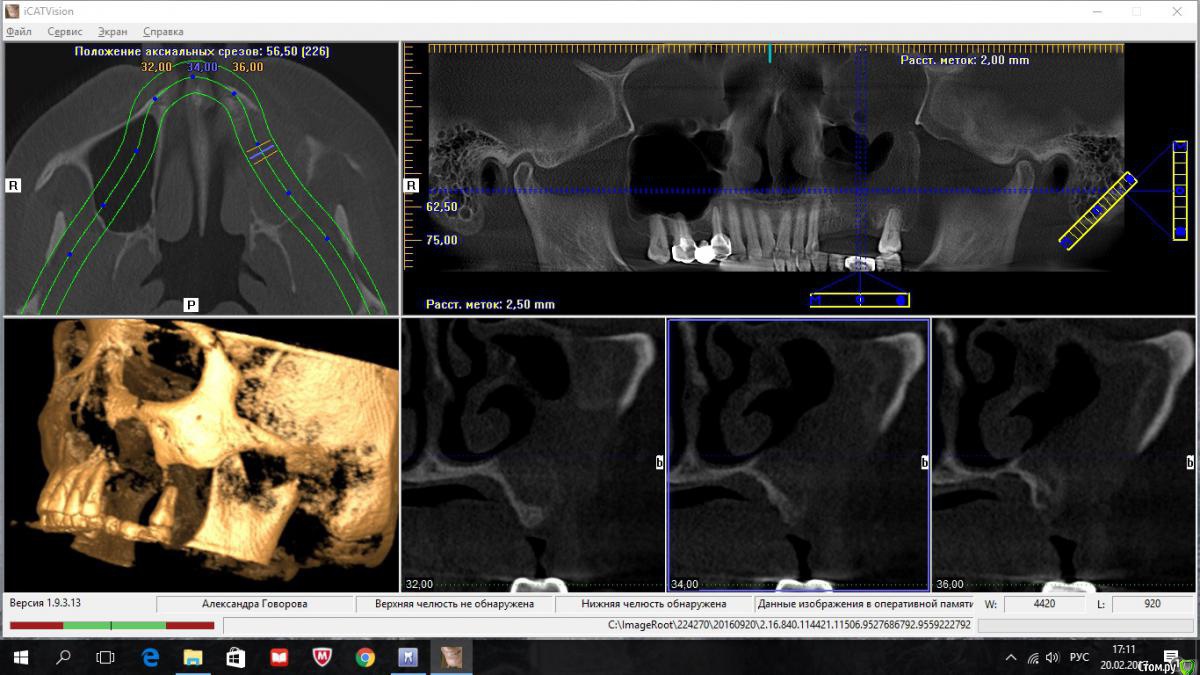

kriokov Опубликовано 20 февраля, 2017 Поделиться Опубликовано 20 февраля, 2017 пациентка 56 лет Радикальная гайморотомия в чло в сентябре 16.Удален 16. клкт до экзекуции клкт спустя месяц клкт примерно через полгода 2 Ссылка на комментарий

kriokov Опубликовано 20 февраля, 2017 Автор Поделиться Опубликовано 20 февраля, 2017 А разве Колдуэлл-Люк тут сильно виноват?не знаю, смотря что кто видит на снимках. Изначально--клиники синусита не было, смотрел пациентку на предмет иплантации во 2 сегменте, увидел рентгенологически тень с куполом в пазухе слева, 26 был живой на тот момент, отправил к лорикам, лорики в чло, кафедральные посмотрели- отпунктировали, вроде как получили кистозное наше содержимое. Соперировали.Посмотрел ее через месяц после гайморотомии. Нос дышал, чувствительность выпала, парус во рту по своду, но не критично. Решил подождать 6 мес.И вот сейчас картина -- клиники гайморита нет, дышит. Чувствительности нет, не восстановилась. По своду понятно- все как было. А вот рентгенологически картинка интересная-- там где не закрывалось латеральное окно, мягкие ткани туда и ввалились (наверное что на подобие рубцовых тканей), киста судя по всему была, как раз почти по верхней границе купола идет рост новообразованной кости. Кость по высоте 10-12 мм в обл 24 , 25, 26. Кто виноват (Колдуэлл или Пушкин) мне по барабану, я не эксперт, и не кафедральный. Думаю, если бы была возможность латеральное окно сеткой или мембраной перекрыть, пролапса мягких тканей внутрь не было бы. Ну и из разряда экзотики-- можно и на одном столе отработать члх и лорику. ИМХО 2 Ссылка на комментарий